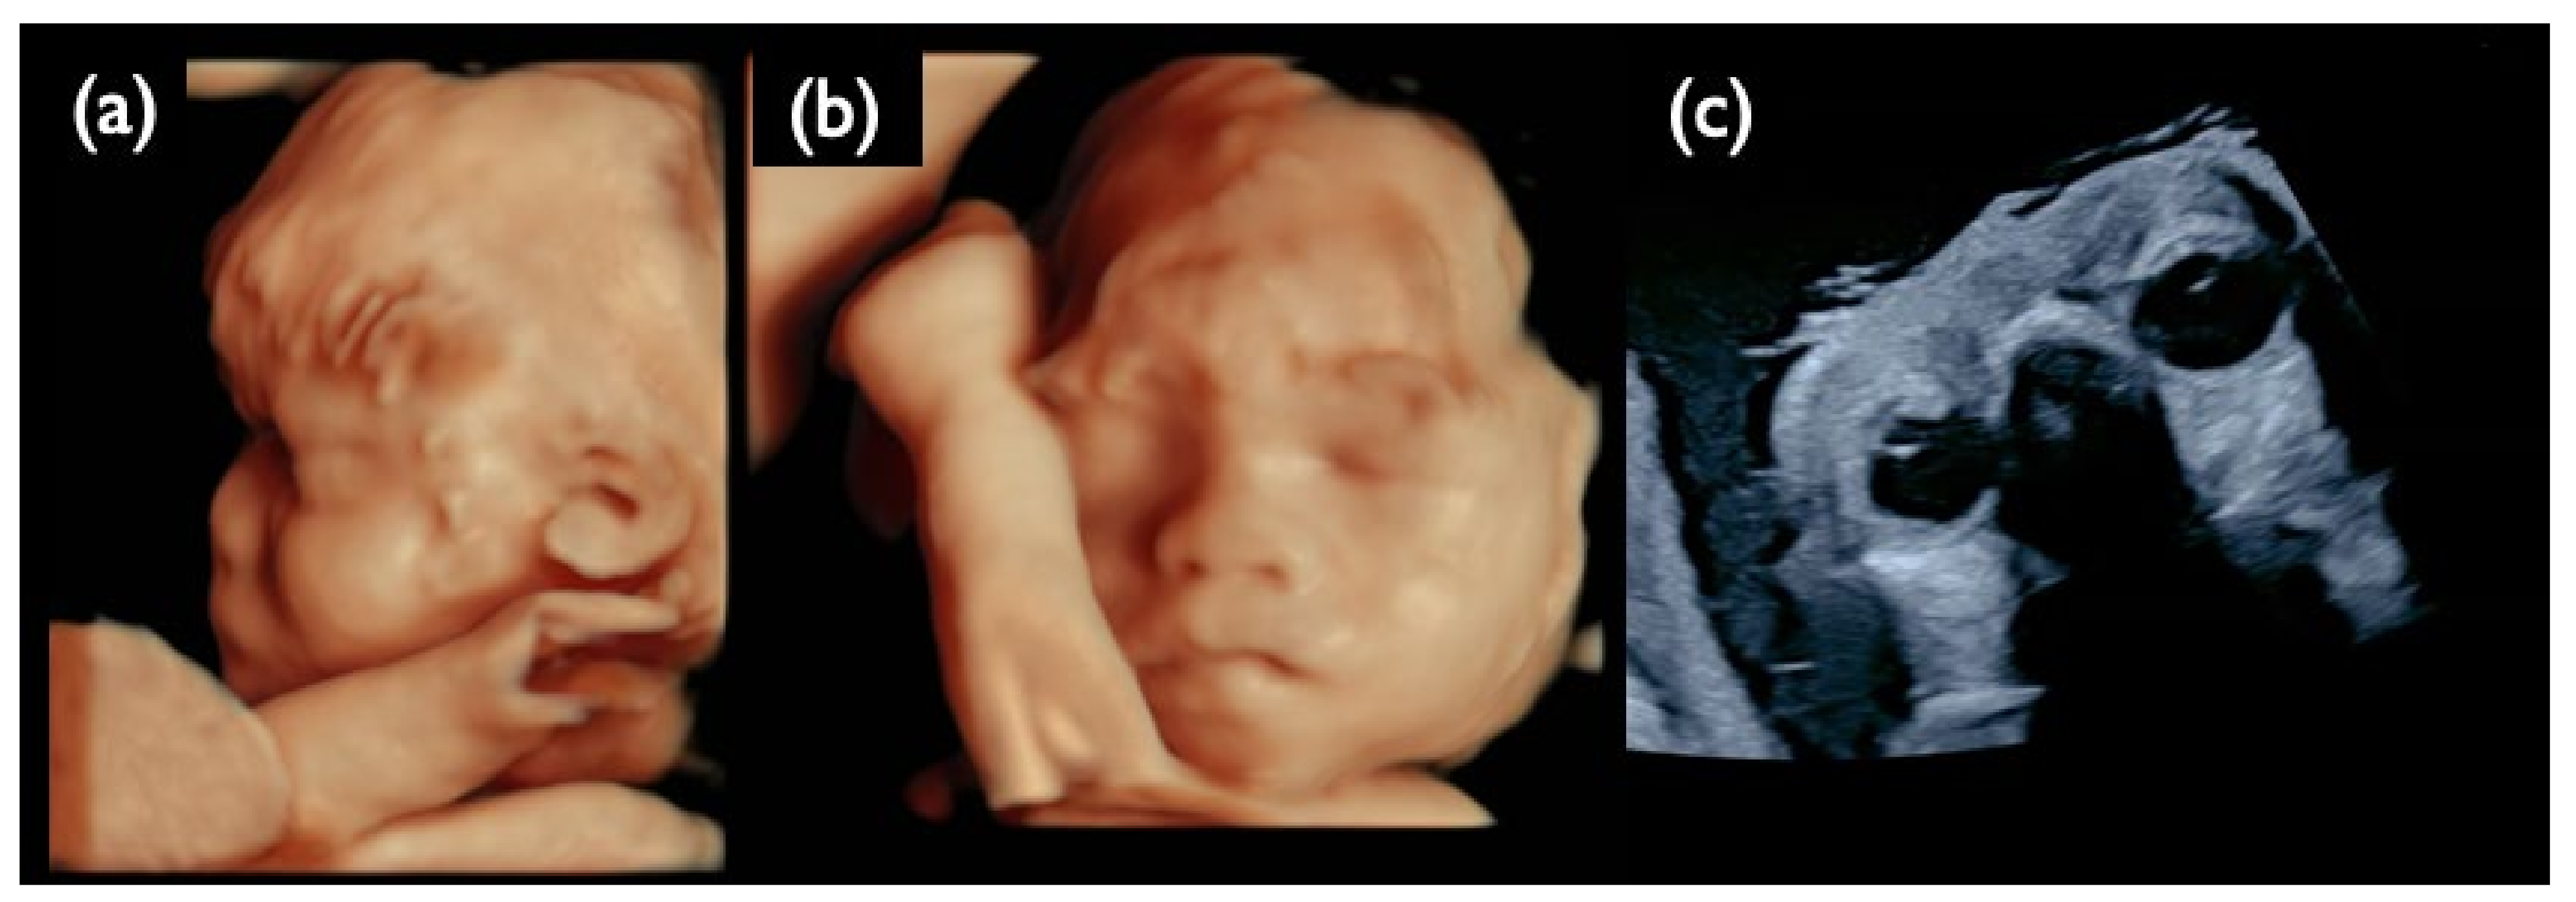

| Chromosome 18 relevant mosaicism | Mo5 | 13 + 5 | XX,+18 Mosaicism | T18 (56%) | 47,XX,+18/46,XX (44%/56%) | – | – | T18 Negative | 2.09 | + | 8.3 | Increased NT, GE moderate, Small NB, Micrognathia, Lowset ear, T18 like profile, Wrist contracture bilateral, Cardiomegaly, Large VSD, TR severe, MR severe, Stomach invisible, Hyperechoic bowel, DV reversed flow, SUA, Umb.A.reverse, T18 is strongly suspected, |